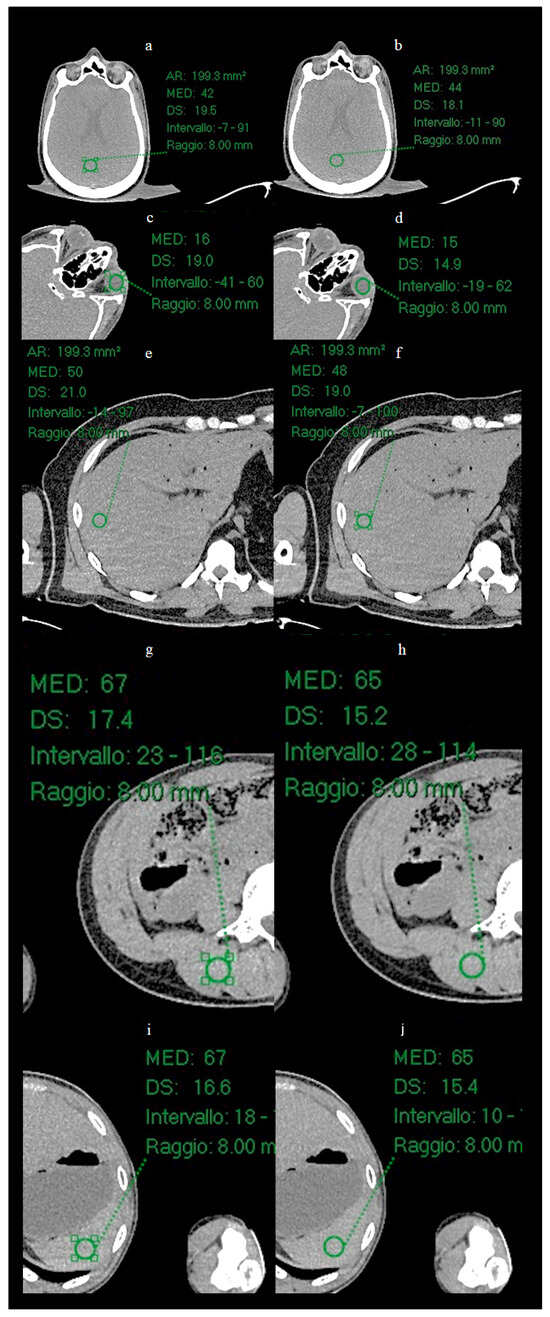

3.2. ROI Results

Circular ROI of radius 8 mm were placed on the images of the Test Set on the vitreous body (Figure 6), brain parenchyma, liver parenchyma, splenic parenchyma and paravertebral muscle, and the mean and SD of the mean values of Hounsfield Units (HU) were calculated for each ROI.

Figure 6.

Positioning of ROIs in five anatomical locations for quantitative analysis. Circular ROIs with a radius of 8 mm were placed on: (a,b) brain parenchyma, (c,d) vitreous body of the eye, (e,f) liver parenchyma, (g,h) lumbar paravertebral muscle, and (i,j) spleen parenchyma. For each anatomical location, the image on the left shows the low-dose acquisition, while the image on the right shows the corresponding result processed by ErisNet. These anatomical regions were selected to evaluate ErisNet’s performance on different tissue types and attenuation characteristics. The comparison demonstrates a consistent reduction in the standard deviation of Hounsfield units within the ROIs after processing with ErisNet (Table 4).

The mean values of measured ROI are shown in Table.